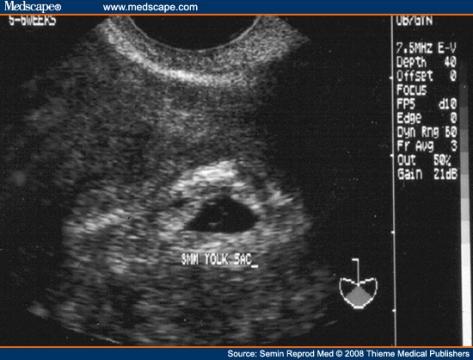

Dobrý deň! Mám istý problém a rada by som sa spýtala na Váš názor. Tento mesiac 7. 9. 2011 som bola u gynekologičky na ultrazvuk a odber krvi, keďže som tehotná. Podľa výpočtu od poslednej menštruácie som bola vtedy v 5 tt + 4. Lekárka na ultrazvuku videla už embrionálne štruktúry, vyzeralo to ako bublinka (asi tak ako na priloženej fotografii - nie je to však môj ultrazvuk, len na porovnanie). Vystavila mi tehotenský preukaz, povedala mi, aby som sa objednala v októbri na integrované testy a ďalšiu návštevu, teda aj ďalší ultrazvuk mi dala až 10.10. 2011, čo budem už v 10 tt + 2! Podľa môjho názoru je to dosť neskoro, veď srdiečko vidno biť oveľa skôr, už vraj v 7 tt a ja mám prísť až tak neskoro? Čo ak srdiečko biť nebude a ja budem nosiť mŕtvy plod? Je takýto postup gynekologičky správny? Už som po jednom missed abort (zamlčanom potrate) z roku 2010 a chcem sa vyvarovať možných rizík. Ďakujem Vám za radu. S pozdravom Zuzana